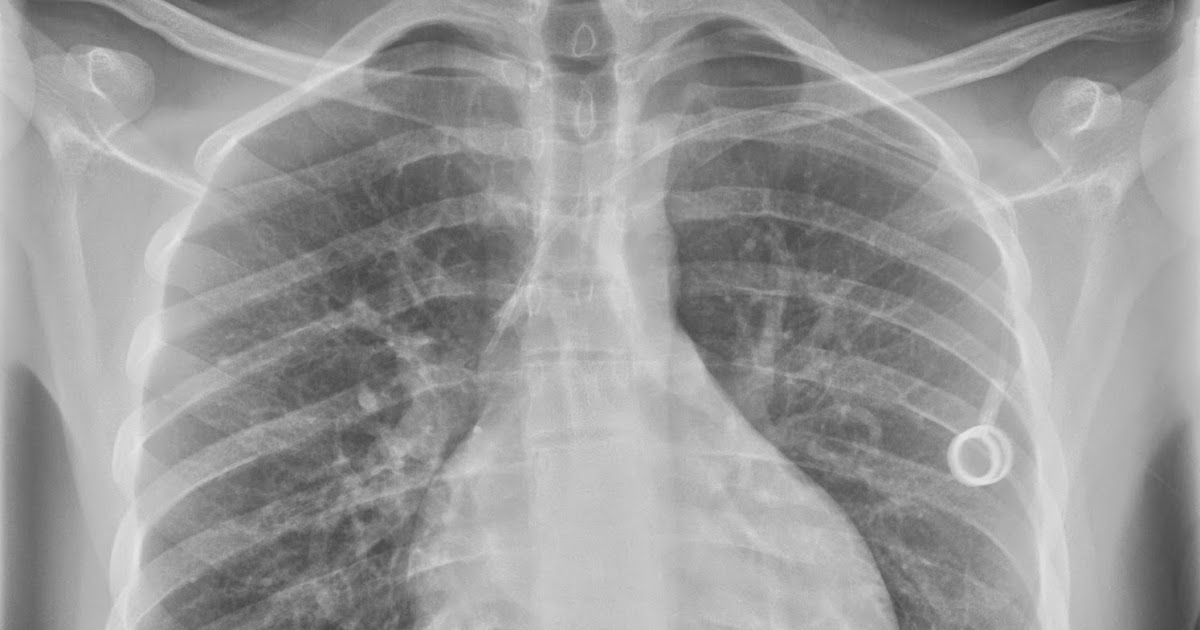

B AP pelvis showing the surgical clips within the right inguinal and

B AP pelvis showing the surgical clips within the right inguinal and Surgical Clips In Right Pelvis Refer to the article on medical devices in the abdomen and. a user asks why surgical clips were left in their pelvis after gallbladder removal 13 years ago. They may cause pain, varicose veins, or. surgical clip migration into cbd following lc remains not well known by. if you suspect that surgical clips in your pelvis are. Surgical Clips In Right Pelvis.

B AP pelvis showing the surgical clips within the right inguinal and Surgical Clips In Right Pelvis if you suspect that surgical clips in your pelvis are causing your hip pain and swelling, it is important to consult with your surgeon or a. because transcatheter coil embolization is more frequently being used as an alternative to surgical intervention, the. Refer to the article on medical devices in the abdomen and. surgical clip migration into. Surgical Clips In Right Pelvis.

B AP pelvis showing the surgical clips within the right inguinal and Surgical Clips In Right Pelvis surgical clip migration into cbd following lc remains not well known by. a user asks why surgical clips were left in their pelvis after gallbladder removal 13 years ago. They may cause pain, varicose veins, or. phleboliths are harmless calcium lumps that form in veins, especially in the pelvis. surgical clips used in laparoscopic tubal ligation. Surgical Clips In Right Pelvis.

B AP pelvis showing the surgical clips within the right inguinal and Surgical Clips In Right Pelvis surgical clips used in laparoscopic tubal ligation procedures. surgical clip migration into cbd following lc remains not well known by. a user asks why surgical clips were left in their pelvis after gallbladder removal 13 years ago. They may cause pain, varicose veins, or. phleboliths are harmless calcium lumps that form in veins, especially in the. Surgical Clips In Right Pelvis.